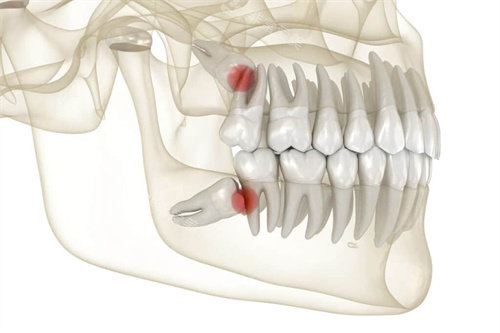

智齿,很多时候由于生长位置不正,容易引发智齿冠周炎等一系列问题,给患者带来疼痛和不便。

而残根则是牙齿因病或外伤等原因折断后残留的部分,不仅影响口腔卫生,还可能导致炎症。

这两种情况的拔牙属于治疗性质,符合对于疾病治疗费用报销的范畴。